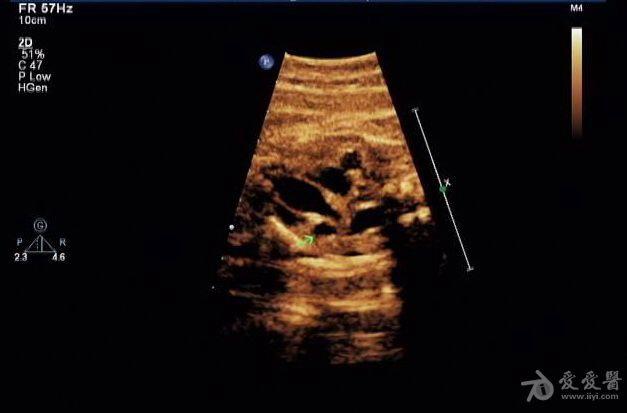

胎儿永存上腔静脉

冠状静脉窦增宽约

0.8 cm

,心底部三血管切面显示肺动脉左侧管腔样结构,频谱显示为静脉频谱。